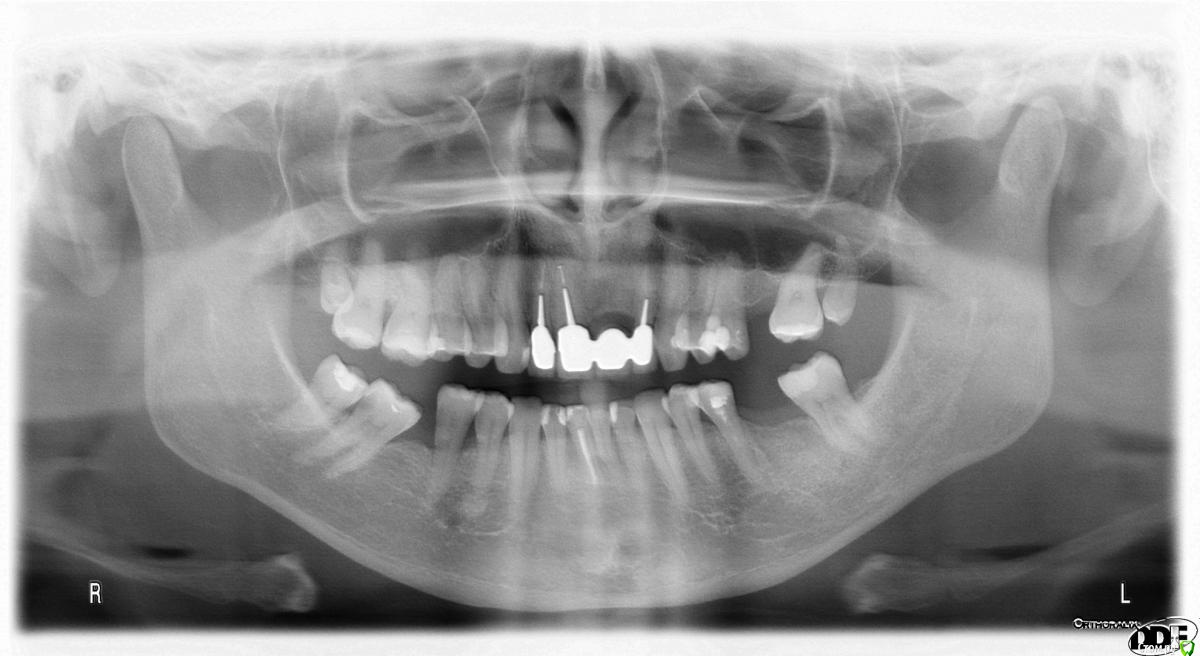

LENalena1965 Опубликовано 1 октября, 2015 Поделиться Опубликовано 1 октября, 2015 Прошу вас помочь! Вопрос в следующем. Планирую протезирование на начало ноября 2015 г. Снимок приложен. Была на консультации у протезиста. Предлагает начать слева. Верх соединить мостиком 7+5. Низ также. Внизу 5-ка розового цвета, пломбировалась в далеком 1995 г. Материл- Безметалловая керамическая коронка. Перед протезирование удаление верхних 8, они очень маленькие. Врач сказал, что там образуются карманы, и может развиться кариес. После этого заняться протезированием правой, а именно удаление 8, выравнивание 7, далее удаление 5, и затем установка мостика. Левая часть обтачивается на живых зубах. Хотелось бы узнать, почему не удаляются нервы в зубах, которые протезируются. Далее смущает материал, вернее его долговечность. Все таки это жевательные зубы. Спасибо! Ссылка на комментарий

red_butler Опубликовано 1 октября, 2015 Поделиться Опубликовано 1 октября, 2015 1. Консультация ортодонта2. Профессиональная гигиена3. Терапевтическая санация4. Перелечить 3.55. Удалить мудрые зубы6. Ортодонтическое лечение7. Имплантация 2.6 3.6 4.68. Протезирование имплантов и 3.5 1 Ссылка на комментарий